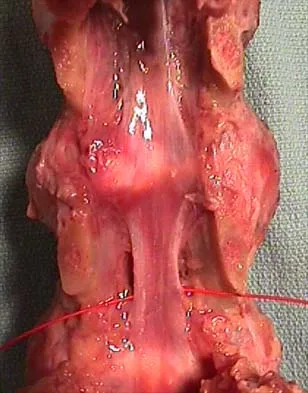

Figures 31a and 31b show the T1- and T2-weighted MRI scans of a patient's knee joint. What is the most likely diagnosis?

Explanation